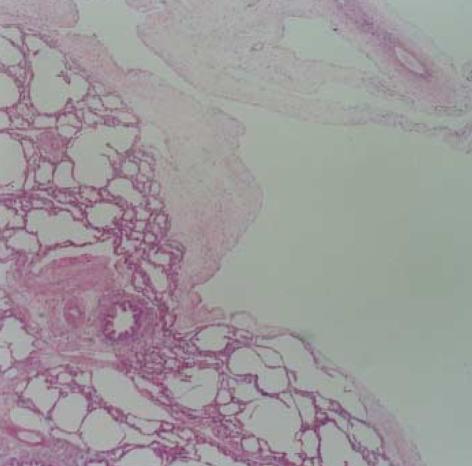

Lymphangioma is an abnormal collection of lymphatics that are developmentally isolated from the normal lymphatic system. Lymphangioma rarely presents as a solitary pulmonary lesion. We report a rare case of intrapulmonary cystic lymphangioma involving the upper lobe of the right lung, which presented with dyspnea in a 2-month-old infant. High-resolution computed tomography (HRCT) of the chest demonstrated a well-circumscribed, multiseptate, cystic lesion in the upper lobe of the right lung, mimicking the feature of type I congenital cystic adenomatoid mal-formation. The tumor was removed by bilobectomy of the upper and middle lobes of the right lung, and its pathologic examination confirmed the diagnosis of an intra-pulmonary cystic lymphangioma.

淋巴管瘤是淋巴管的异常聚集,在发育上与正常淋巴系统隔离。淋巴管瘤很少表现为孤立的肺部病变。我们报告一例罕见的右肺上叶肺内囊性淋巴管瘤病例,该病例发生在一名2个月大的婴儿身上,表现为呼吸困难。胸部高分辨率计算机断层扫描(HRCT)显示右肺上叶有一个边界清晰、多分隔的囊性病变,类似I型先天性囊性腺瘤样畸形的特征。通过右肺上叶和中叶双叶切除术切除肿瘤,病理检查确诊为肺内囊性淋巴管瘤。